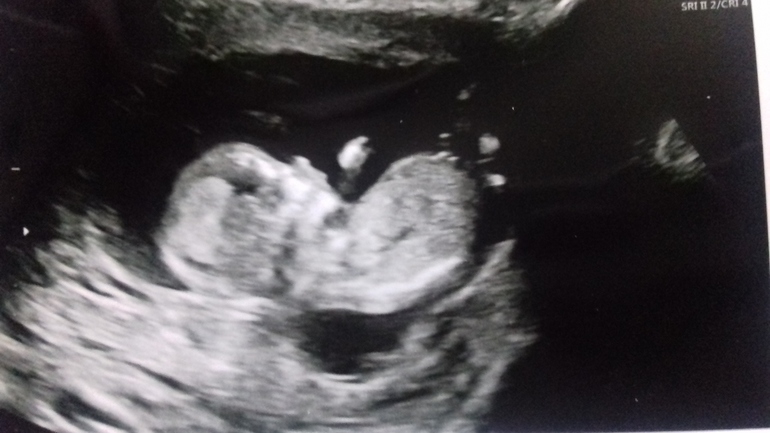

Пол малышаДевочки, подскажите, можно ли по фото предположить пол? А то я вообще в этих узи не понимаю)) 13 недель. Первая беременность, любопытство распирает!)) До второго скрининга свихнусь ))

Терпи казак, атаманом будешь) девчачий нос помоему)))) низ то совсем не видать😁